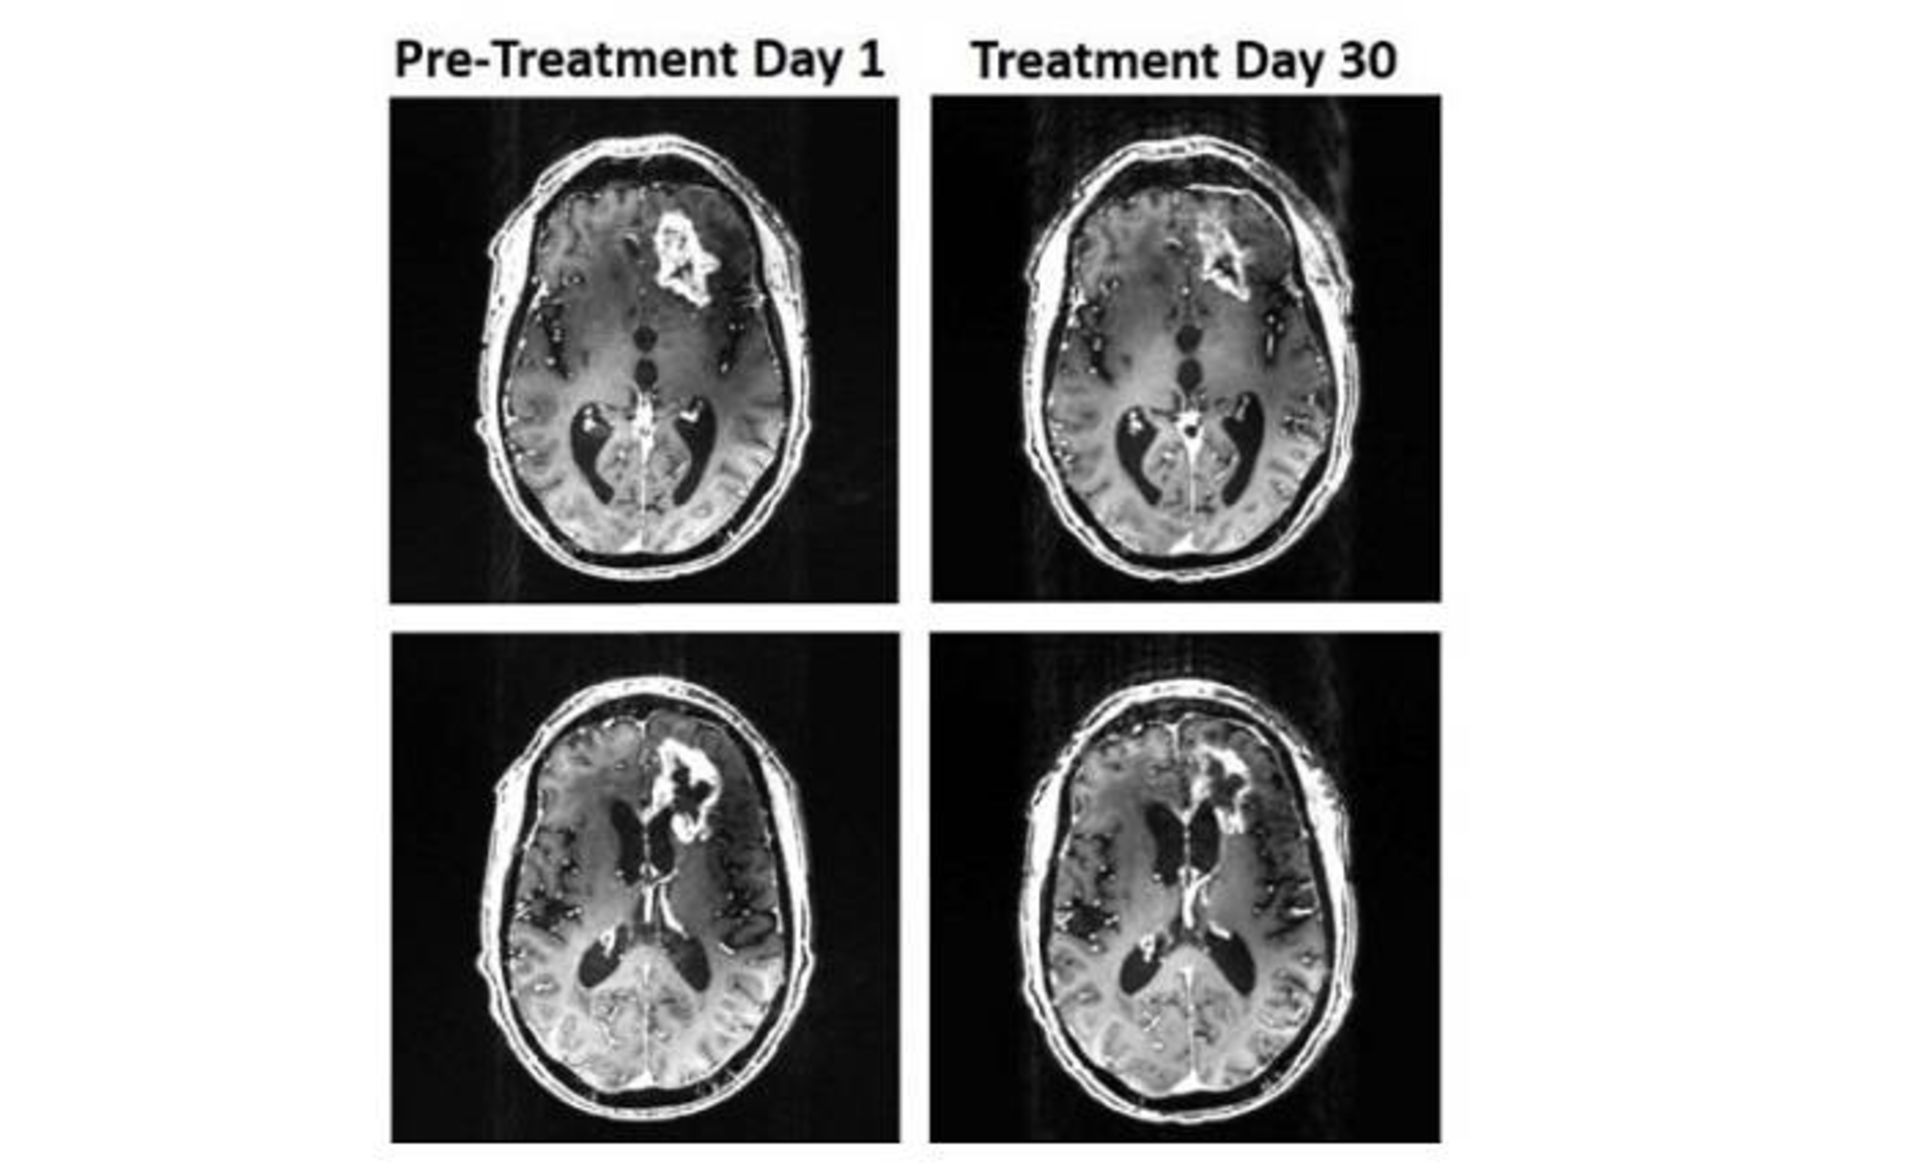

اسکن مغز  / brain scans

اسکن‌های مغز که کوچک شدن تومور را نشان می‌دهد

در کل، درمان به مدت ۳۶ روز ادامه داشت. در این زمان، گلیوبلاستوما ۳۱ درصد کوچک شد و مراقبان بیمار بهبود در گفتار و عملکرد شناختی او را گزارش کردند. پس از ۳۶ روز، درمان از روی اجبار متوقف شد، زیرا بیمار افتاده بود و سرش آسیب دیده بود. متاسفانه، دیری نگذشت که وی از دنیا رفت.